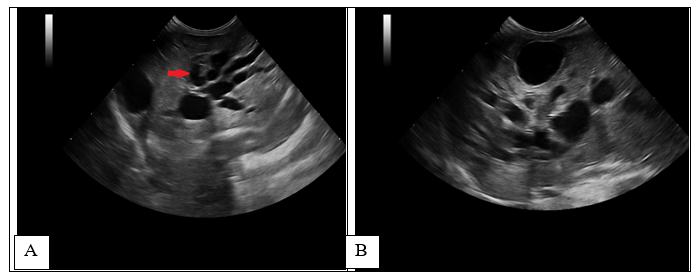

A standard blood test was performed, haematology and biochemistry revealed moderate leucocytosis [WBC-25.96 (2.87-17.02x10^9/L)], mild neutrophilia [12.15 (2.30 - 10.29 x10^9/L)], lymphocytosis [9.53 (0.92 - 6.88 x10^9/L)], monocytosis [1.05 (0.05 - 0.67 x10^9/L)] and anisocytosis, creatinine [17 (53 - 141 µmol/L)], increased ALP [445 (14 - 192 U/L, values for young patients)], elevated GGT [144 (0 - 1 U/L)], bilirubin-total [ 81 (0 - 15 µmol/L)] and lipase [1,214 (40 - 500 U/L)]. The rest of the results were unremarkable. An abdominal ultrasound was, findings revealed moderate hepatomegaly with homogeneous echogenicity. Generalized distended and tortuous ducts (between 5-7 mm) were noted within all liver parenchyma (Figure 1-red arrow), with the gallbladder being identified separately, with normal architecture. In this case, the abdominal distension was mostly caused by the dilated intrahepatic ducts, mimicking hepatomegaly. The common biliary duct was normal, followed up to the level of the duodenum, duodenal papilla was not well identified owing to the amount of ingesta. Mildly thickened biliary duct walls were seen at the level of the central liver. No obvious cause of biliary obstruction was identified. Color Doppler flow was used to confirm the absence of blood flow at the level of distended ducts. Due to the size and age of the patient (400 g and 2 months of age), symptomatic treatment was started with ursodeoxycholic acid10 mg/kg PO q24h, liver supplements based on SAMe (S-Adenosyl-L-Methionine), Silybin, Turmeric extract (Curcumin) and amoxicillin and clavulanic acid, 15 mg/kg PO q12h. Abdominal distension improved after 5 days, but treatment was discontinued after 1 week.

Figure 1 Initial ultrasound examination.

Longitudinal (A) and transverse (B) image of the liver- Diffuse tubulo-saccular dilatation, mostly within the right liver, was noted, with secondary compression of the local hepatic veins and arteries, subsequently causing turbulent and high-velocity blood flow, assessed with PW Doppler. The GB was identified, but in a more lateral position, most likely due to compression and mass effect of the distended intrahepatic ducts.

On abdominal ultrasound, the liver was enlarged and distorted by numerous coalescing anechoic structures. In the absence of a Color flow Doppler signal and localization of the hepatic blood vessels, the structures were presumed to represent intrahepatic biliary ducts.

A follow-up ultrasound performed 4 weeks after the initial examination, revealed an increase in the distention of the intrahepatic bile ducts (> 7 mm) (Figure 2A-white arrow) with echogenic material formation within the ducts (Figure 2B-red arrow), thickening of the gallbladder wall (1.4 mm)10,27 and multilayer pattern (double rim aspect).

Figure 2 1-month follow-up ultrasound scan at the level of the liver (transverse and longitudinal images).

Increased dilatation of the intrahepatic bile ducts, with secondary compression of the local vasculature (A). Dependent echogenic debris is seen within the tubular bile ducts. Following the normal architecture of the bile ducts (localized in the proximity of the liver vasculature), the portal branches were difficult to visualize, causing the intraluminal portal vein sign16,27 (dilated ducts surrounding the portal vein) (Figure 3).